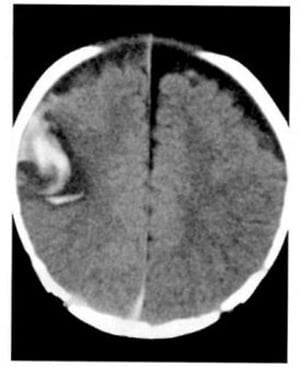

2.7. Máu tụ ngoài màng cứng (Hình 1.45)

Dấu hiệu XQCLĐT:

– Khối ngoài nhu mô, hình thấu kính hai mặt lồi, mật độ cao làm di lệch mặt tiếp xúc lân cận giữa chất xám và chất trắng.

– Thường ở vùng thái dương-đỉnh, ít khi ở vùng trán hoặc chẩm

Hình 1.45. Máu tụ ngoài màng cứng. Khối tụ hình thấu kính hai mặt lồi ở vùng thái dương có mật độ cao tự nhiên, đẩy nhu mô não và xóa mờ não thất bên bên phải.